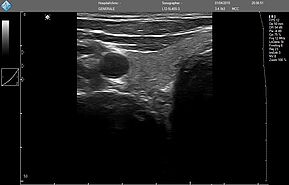

ЗДЕСЬ Вы можете посмотреть реальные кинопетли с аппарата УЗИ MicrUs Pro.